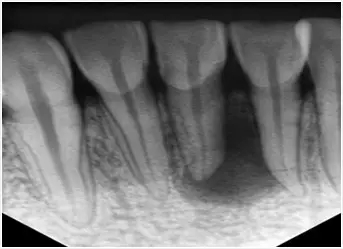

牙齒外層透明的部分叫做牙釉質,牙釉質裏麵偏黃的是牙本質,還有就是牙齒裏麵看不到的中心位置是牙髓腔,裏麵有牙神經和血管。...

通常牙齒壞到牙釉質和牙本質時,可能症狀都不嚴(yan) 重,一旦壞到牙髓腔的牙神經,就會(hui) 出現劇烈疼痛,夜晚疼痛加劇,很多人都無法忍受。

1.拍片 2.開髓 3.確定根管長度